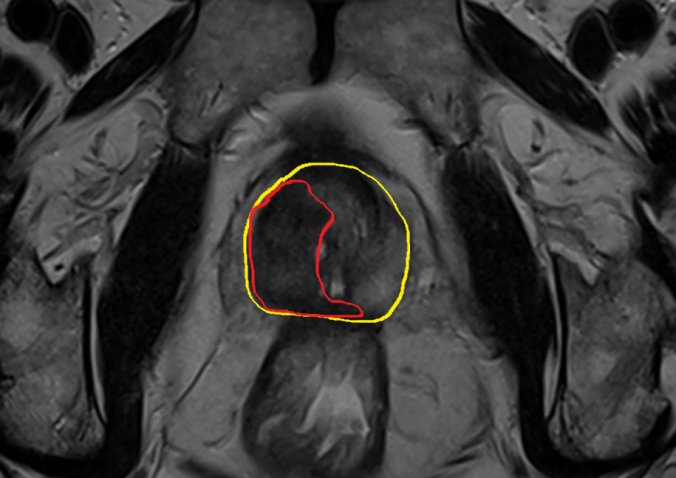

Here are two examples from the front-line which illustrate the problems with the PSA in a screening situation: The first is from a patients who had elevated PSA levels over many years. He had been biopsied several times without any findings of cancer. His PSA was 22 when he was referred to us. We took an MRI of the patient (see picture below) which showed a small, suspect lesion (red line) in an enlarged prostate (outlined by the yellow line).

We took 2 biopsies with our MRI fusion equipment (Artemis, Eigen) and found prostate cancer with Gleason 7a (4mm). Standard biopsies were still negative. There is of course a rationale for treating this patient with surgery or radiation as the cancer is not low-risk and may at some stage cause trouble for the patient if left untreated. There is, however, little doubt that these problems will most likely occur in a rather distant future and his chances of dying of prostate cancer in the next 10-15 years are rather low. He was 72 years old at diagnosis and had several other diseases with potential negative impact on his life-expectancy. In my opinion there is no clear-cut treatment recommendation for this patient. He chose active surveillance.